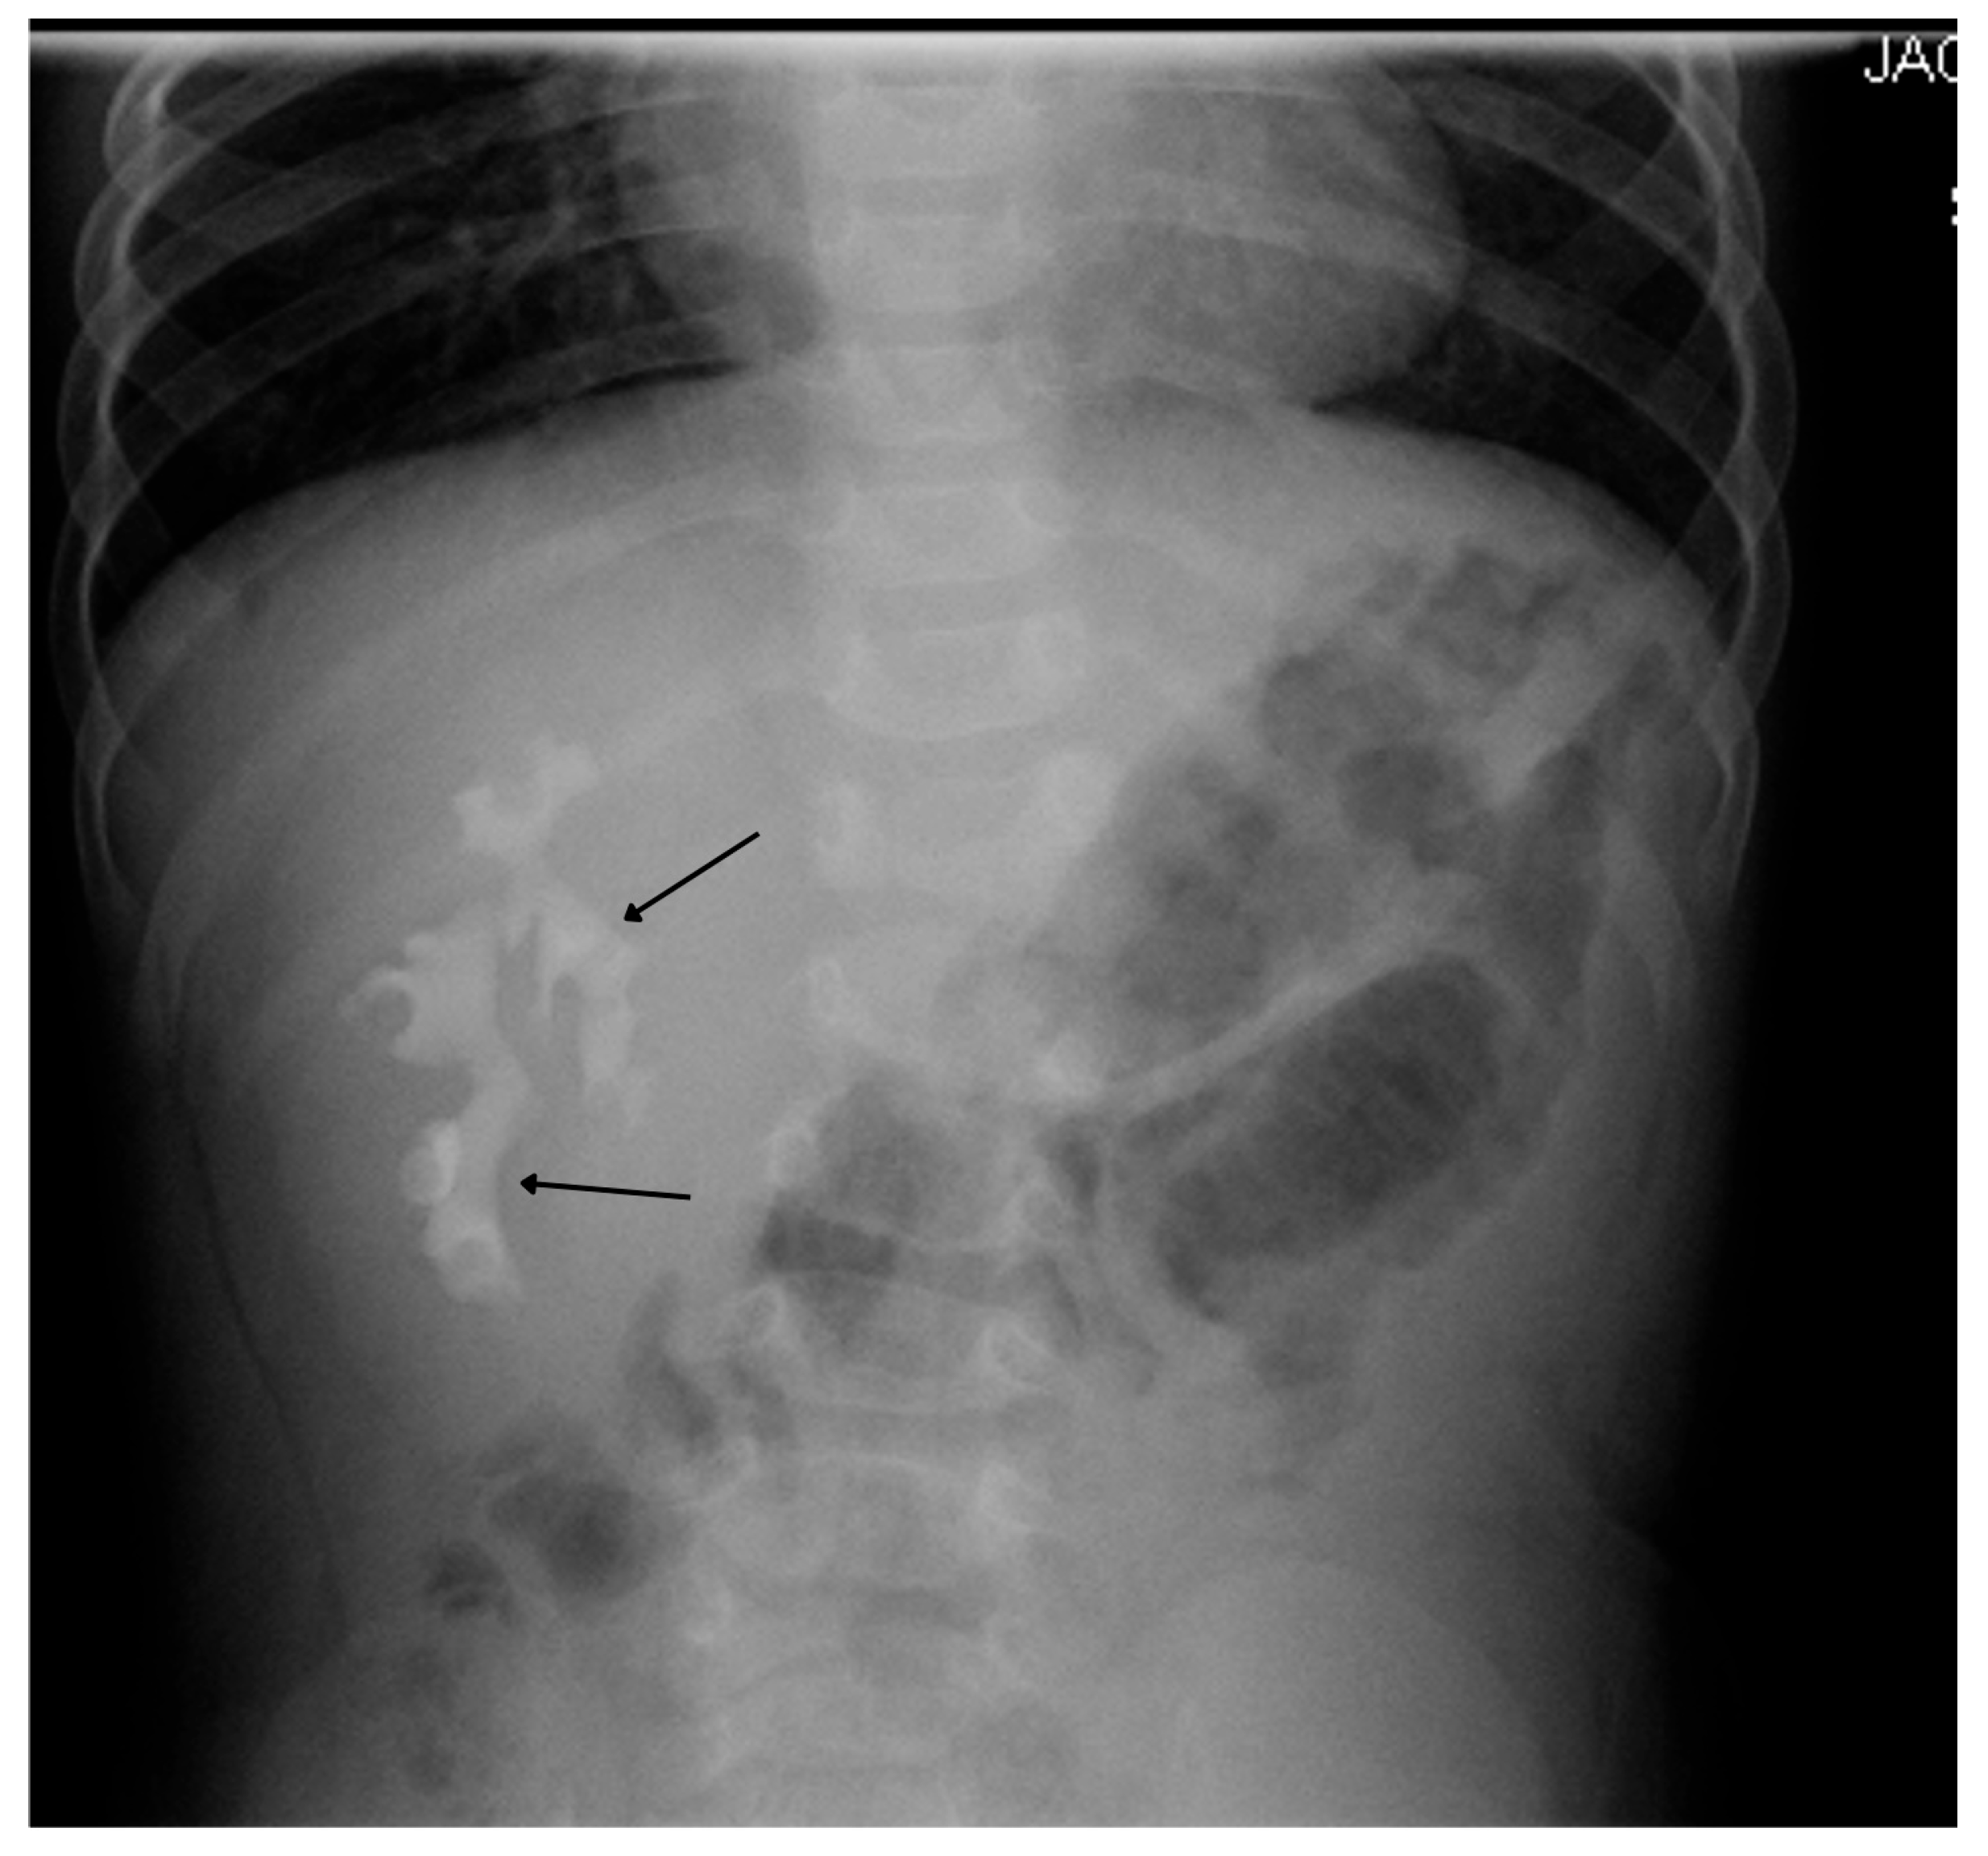

20. Nephrolithiasis

7. Intravenous Pyelography (IVP)

7.1. Technique

7.2. Indications